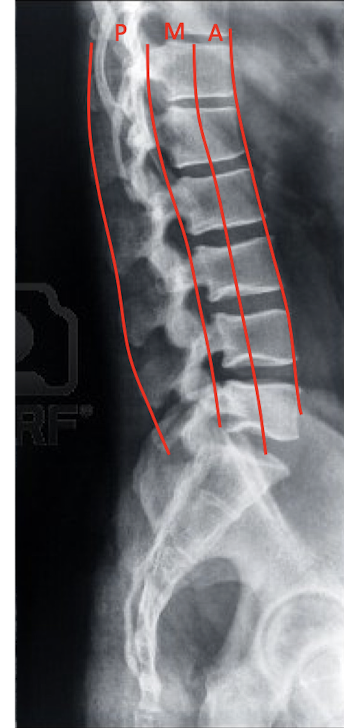

Label these 4 Lines? (C/S)

Define the 3 Column Concept:

Anterior Column

Middle Column

Posterior Column

3 Column Concept:

What structures are included in:

Anterior Column:

2

Middle Column:

2

Posterior Column:

4

Anterior Column

Anterior Longitudinal Ligament

Ant. 2/3 of Vertebral Body

Middle Column

Posterior 1/3 of the Vertebrae

Posterior Longitudinal Ligament

Posterior Column

Posterior Ligament Complex

Vertebral Arch

Facets

Ligamentum Flavum

Spinal Column Rules:

What are the 3 Spinal Column Rules?

Spinal Cord and Canal are located Posterior to the Middle Column in the Posterior Column

Fx in the Posterior and Middle Column have potential to encroach on the Spinal Cord and Canal

MRI is needed to determine the level of injury, if any, to the spinal cord

Notice: Post Vertebrae Intact, Ant Vertebrae w Fx